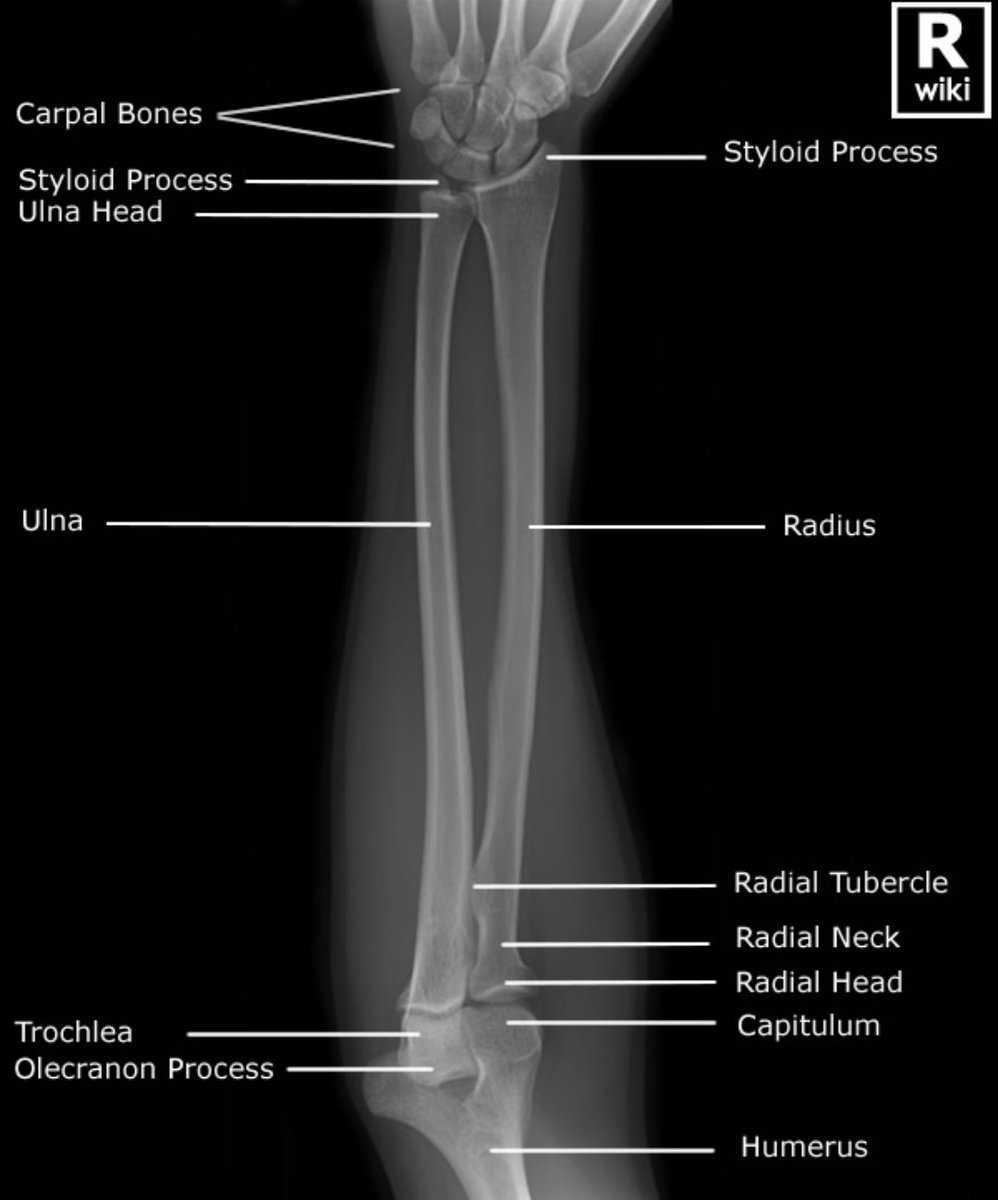

•يتكون من عظمتين:

1.Radius:

تقع باتجاه الإبهام وهي التي تلتف علىulnaفي وضع prone.

وتعتبر الأقصر.

2.Ulna:

تقع باتجاه الخنصر وحركتها محدودة عند التفاف اليد وتعتبر أطول.

•يوجد مفصل قريب وبعيد يربط العظمتين مهم لحركةاليد و الرسغ.

•Radius

هي العظمة الوحيدة التي يتضمنها مفصل الرسغ بشكل مباشر.

•Ulna

رأسها و styloid process

يقع عند نهايتها البعيدة(distal end)

وهو البروز الذي نشعر به ونراه باتجاه الأصبع الصغيرة (الخنصر)

عندما تكون اليد في وضع prone.

(جربها وتحسس البروز)

واسمه الكرسوع بالعربي.

الوضع AP forearm

•في تصوير العظام الطويلة لا بد أن نشمل مفصلين وإذا لم يمكن فنشمل المفصل الأقرب للإصابة.

•يكون الكتف و المرفق على مستوى وامتداد واحد.

•يجب أن يكون الساعد ممدود وفي وضع supine.

•وينبغي عدم تصويرها في وضع prone

حتى لاتتقاطع العظمتين.

نقد الصورة:

في الوضع الجانبي:

•لابد أن نشاهد مفصل المرفق يشكل زاوية ٩٠°.

•لايوجد إلتفاف عن طريق مشاهدة:

رأس ulna(البروز العظمي الذي ذكرناه سابقاً)

متراكب مع نهاية عظمة Radius.

•عظمتي humeral epicondyles متراكبة.

•رأس Radius متراكب معcoronoid process

وظهور radial tuberosity